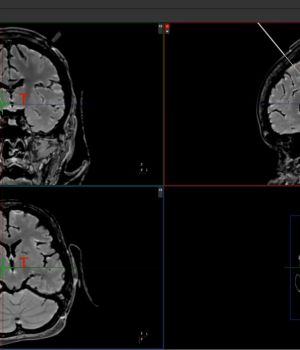

Ziel des geplanten Forschungsprojektes THSpro ist die Entwicklung eines Softwaretools zur Zielpunktplanung für die Tiefe Hirnstimulation mit hohem Marktpotenzial. Aus Messdaten der diffusionsgewichteten Magnetresonanztomografie werden unter Nutzung der probabilistischen Traktografie die neuronalen Faserbahnen im Gehirn rekonstruiert. Anhand dieser neurologisch-funktionalen Daten wird der Zielpunkt der Tiefen Hirnstimulation bestimmt. Sie wird die Genauigkeit der Zielpunktfindung verbessern und so direkt dem Patientenwohl dienen. Die prozessgesteuerten Handlungsabläufe des Planungsvorgangs werden auf Zeit-, und damit Kostenersparnis, optimiert. Die Schulung und Bedienhilfe wird mit einem interaktiven Videointerface effizient realisiert. Eine eigens konzipierte VSEO-Strategie wird Experten und Betroffene helfen sich umfassend zu informieren.

Methoden des maschinellen Lernens werden eingesetzt, um die zeitaufwendigen Berechnungen der probabilistischen Traktografie zu verkürzen. Dies bedeutet einen zeiteffektiveren Planungsvorgang und spart Kosten.